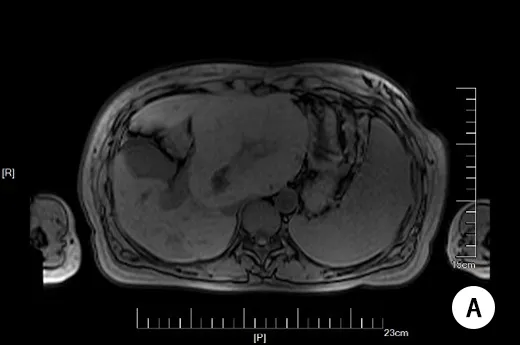

aminotransferase,AST)37.8μmol/L,门诊予熊去氧胆酸胶囊250mg tid口服,定期复查相关指标。 孕20周开始出现皮肤瘙痒,2023-03-31(孕20+6周)因TBA及肝酶异常病情控制不佳住院。住院期间予思美泰静滴、熊去氧胆酸口服治疗,监测相关指标,因肝胆胰脾B超提示肝左叶占位,完善多学科会诊,遵会诊意见完善肝脏+肝血管超声、MRI、全外显子基因检测和切片会诊等,规律复查肝酶及TBA,孕34+2周入院待产。现患者偶有皮肤瘙痒,无腹痛腹胀及阴道流血流液等不适,无纳差、乏力,两便正常。 【既往史】 既往体健,否认高血压、糖尿病、肾病病史,否认肝炎、结核等传染病史。无外伤史。否认食物药物过敏史。 手术史:2013年剖宫产术,2010年于老家市立医院因肝脏占位行开腹肝V、VI、VII段切除术,术中见肿瘤位于右肝,大小约12cm*10cm,有包膜,完整切除肿物,病理结果为病理结果示镜下见肝细胞增生,正常结构消失,部分区域肝细胞轻度异型,结合免疫标记结果CD34+血管丰富,不排除高分化肝细胞性肝癌。 免疫标记(2010-2803):CD34+、Gpc-3-、AFP-、CD10-、Ki-67+约3%。(建议外会诊进一步确诊)后自诉复旦大学附属中山医院病理科会诊结果为良性,遂未进一步随访。 【婚育史】 1-0-1-1(2013年外院剖宫产一男婴,重3400g;2018年因个人因素药流)。适龄结婚,配偶及1子体健。 【月经史】 初潮12岁,5/30日,量中,无痛经。 【家族史】 否认家族遗传病史及类似疾病史。 【入院后的检查检验】 查体: T:36.8℃,BP:106/69mmHg,P:80pm,R:20次/分,身高168cm,体重74kg,BMI:26.22kg/m2。神清,精神可,皮肤粘膜无黄染,全身浅表淋巴结无肿大,全身无浮肿,瞳孔等大等圆,对光反应好,巩膜无黄染,甲状腺无肿大,心肺听诊无异常,腹软,膨隆,肝脾肋下未及。脊柱四肢无畸形,生理反射存在,病理反射未引出。外阴无浮肿,无静脉曲张,无疤痕。产科检查:宫高:30cm,腹围:100cm,估计胎儿大小:2800g,胎方位:LOA,胎心:152次/分。 辅助检查: 2023-04-01,肿瘤全套(女性):甲胎蛋白57.18μg/L,肿瘤特异生长因子75.40U/mL;血凝常规、输血常规、自免肝组合均未见明显异常。 2023-04-01,肾输B超:右肾异常回声,考虑错构瘤可能。左肾及双输未见明显异常。 2023-04-01,肝胆胰脾B超:肝内多发实性占位性病变,其一大小约139mm*107mm,位于左叶,肝K?,建议超声造影,胆囊息肉,建议随访,脾脏肿大。 2023-04-06,肝脏+肝血管超声:肝左叶实性占位性病变,FNH?门静脉右支及肝右静脉回声异常,考虑门体侧枝循环开放,肝动脉流速增高。 2023-04-24,MRI:肝左叶见类圆形等T1等T2信号,内可见条片状稍长T2信号,大小约125mm*113mm,DWI呈等稍高信号,信号不均,其内见疤痕样改变,门脉及肝静脉呈受压改变,肝右叶见迂曲扩张静脉血管影。提示肝左叶占位,门脉及肝脉受压改变,FNH可能;建议普美显增强检查;肝右叶异常增粗静脉血管影。脾大。 2023-04-29,全外显子基因检测报告示:未检出与受检者临床表型相关的致病/疑似致病变异/遗传模式相符的临床意义未明变异。在Meckel综合征7型/肾-肝-胰腺发育不良1型/肾单位肾痨3型相关的NPHP3基因上检出与受检者表型部分相关的1个疑似致病变异。在肾单位肾痨16型相关的ANKS6基因上检出与受检者表型部分相关的2个意义未明变异。在严重的先天性肝病相关的FOCAD基因上检出与受检者表型部分相关的1个意义未明变异。在家族进行性肝内胆汁淤积6型相关的SLC51A基因上检出与受检者表型部分相关的1个意义未明变异。 图1:孕期MRI平扫 A:T1; B:T2; C:DWI 【入院诊断】 1.妊娠期肝内胆汁淤积症; 2.肝占位性病变:FNH? 肝脏恶性肿瘤?; 3.妊娠合并子宫瘢痕; 4.妊娠合并人类乳头状瘤病毒感染; 5.G3P1孕34+2周LOA待产。 鉴别诊断: 2.肝血管瘤:良性,常见病史为先天发育异常,症状有上腹不适、腹胀、嗳气,腹部肿块、光滑、柔软,CT可见肝内占位,增强CT“早出晚归”。 3.肝腺瘤:良性,发生在中青年女性,患者长期服用口服避孕药,肝腺瘤可能发生破裂、出血、转变成恶性病变。 4.再生结节(肝硬化结节):发生于肝硬化的患者,肝硬化患者在肝脏进行性纤维化的过程中会出现再生结节。 5.原发性肝癌:常见病史为乙肝、肝硬化,症状有,肝区疼痛、乏力、消瘦,肝大、右上腹包块,凹凸不平,CT可见肝内占位,增强CT“快进快出”。 6.转移性肝癌:单个或多个肿块/结节,有肝外恶性肿瘤(如结肠癌,胰腺癌),AFP一般不高。 7.肝包虫病:常见病史为疫区居住,症状有上腹不适、隐痛,腹部囊性肿块、肝大、无触痛,CT可见肝内占位,环行钙化。 8.肝脓肿:常见的肝脓肿有细菌性和阿米巴性两种。 患者育龄期女性,已婚已育,隐性起病,因“发现总胆汁酸升高”就诊。既往肝脏肿瘤病史,术后切片病理恶性不能排除,孕期发现肝内多发实性占位性病变,左叶其一大小约139mm*107mm。肿瘤指标未见明显异常。 于孕34+3周在连续硬膜外麻醉下行子宫下段剖宫产终止妊娠。剖宫产后65天在全麻下行部分肝切除术。 因既往肝脏手术史,恶性不能除外。故借病理蜡块我院病理科会诊提示高分化腺癌。再次送中山医院病理科会诊提示:(右肝)肝细胞增生性病变,伴大量血湖及畸形血管,符合局灶结节性增生改变。结合影像及皮肤瘀点,不排除遗传性毛细血管扩张症致肝脏病,遂完善腹部MRI及全外显子基因检测等。 孕32+3周行多学科会诊,普外科、消化科、影像科、超声科、病理科、产科联合会诊意见: 根据患者目前影像学指标,从核磁结果来看,因孕期普美显造影受限,肿块弥散成像未见明显弥散受限,不支持恶性肿瘤。核磁可见血管畸形,门脉和肝中静脉吻合,门脉进入肝内后增粗明显,提示可能门脉和体循环肝静脉吻合支,FNH也好发有血管畸形不能,故排除先天性或手术后改变。从超声结果来看肿块较大,肝脏质地尚可,门脉主干不宽。就肿块形态和整体表现,中央轮辐状血流明显,整体考虑FNH可能性。但是确实需要和高分化腺癌进行鉴别。现肿块较大,相对于超声而言,核磁测量相对比较准确。建议MRI动态监测是否有明显变化。 从病理科角度来看,FNH和高分化腺癌很难区别,中山医院会诊结果为符合局灶结节性增生改变,就免疫组化结果,我院的病理诊断和患者手术医院的结论相符合。仍不能排除高分化腺癌的可能。是否可以和十年前的结果用一元论解释,建议分娩后再次针对该次肿瘤的病理检查。 既往我院有类似病例,结合既往无肝炎病史,无肝硬化基础,无酗酒史,除十年前手术史以外,无其他既往肝病基础,肝功能正常,且病程相对比较长,考虑本次肝脏占位首先考虑FNH可能性大。就该病而言,现无门脉高压表现,不影响终止妊娠的时机。建议产后专科完善相关检查后评估后续肝脏手术时机和方式。 针对目前胆汁淤积,现已经对症进行处理(优思弗,思美泰足量治疗),可考虑加用激素治疗,甲强龙40-60mg/d,注意对症支持处理。如果有效,3天左右可以监测到胆汁酸明显下降。如果无效,可以按产科ICP处理。产后完善普美显增强造影,根据结果评估后续诊疗方案。 针对TBA增高,先后采用口服熊去氧胆酸胶囊(优思弗)250mg tid,静滴思美泰0.5g qd保肝,多学科联合会诊(Multi-disciplinary team,MDT)后加用甲泼尼龙40mg口服治疗,07-02(孕34+1周)复查TBA49.5μmol/L。 考虑患者重度ICP,合并肝脏不明性质的占位性病变,与患者及家属充分沟通后于孕34+3周在连续硬膜外麻醉下行子宫下段剖宫产终止妊娠。术中取耻骨联合上三横指原疤痕部位横切口,长约12厘米,进腹探查见:子宫轻度右旋,下段形成一般,膀胱与子宫前壁粘连,横形切开子宫下段,见羊水清,量约1000ml,手托头顺利娩出一女婴,2400g,Apgar评分10-10分,清理呼吸道后交台下处理,因“早产儿”后续转儿童医院进一步诊治。胎盘胎膜自娩完整,顶端加固后常规缝合子宫。术中按摩子宫及缩宫素宫体注射后子宫收缩可,出血共约300ml,探查双侧附件未见明显异常。检查子宫下段切口无活动性出血,脂肪,肌肉及皮肤多处渗血,严密缝合止血后未见活动性出血。清点纱布器械无误,逐层关腹,安返病房。术后阴道检查,宫口未开,阴道内积血约20ml。保留导尿清。 术后诊断: 1.妊娠期肝内胆汁淤积症; 2.肝占位性病变:FNH? 肝脏恶性肿瘤?; 3.妊娠合并子宫瘢痕; 4.妊娠合并人类乳头状瘤病毒感染; 5.早产; 6.G3P2孕34+3周LOA剖宫产。 剖宫产术后第四天,患者一般情况好,阴道出血不多。查体双乳不胀,腹部切口干燥,无红肿硬结,腹软,无压痛反跳痛,宫底脐下两指余。予出院。 出院后患者随访TBA及肝酶恢复正常。2023-08-31(剖宫产后58天)入住我院普外科。 完善术前常规检查及肿瘤全套:甲胎蛋白<2μg/L,癌胚抗原1.95ng/mL,糖类抗原CA199